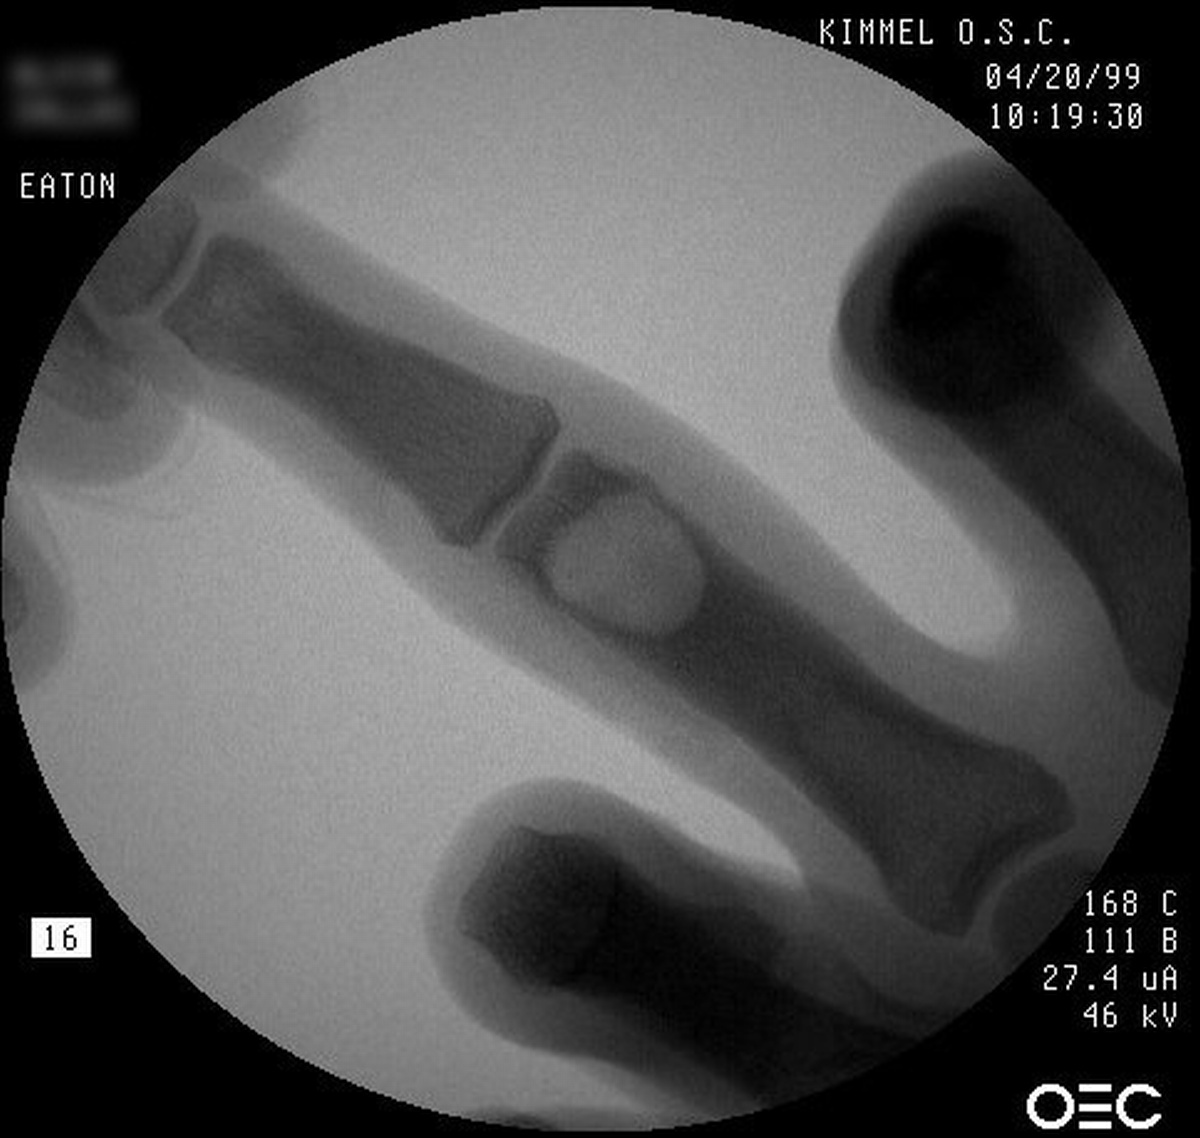

| Case 1. This 18 year old man

presented with a two year history of pain and swelling of the distal

aspect of his proximal phalanx. |

| Plain films showed

sclerosis within a radiolucent area and adjacent cortical/endosteal

sclerosis. |